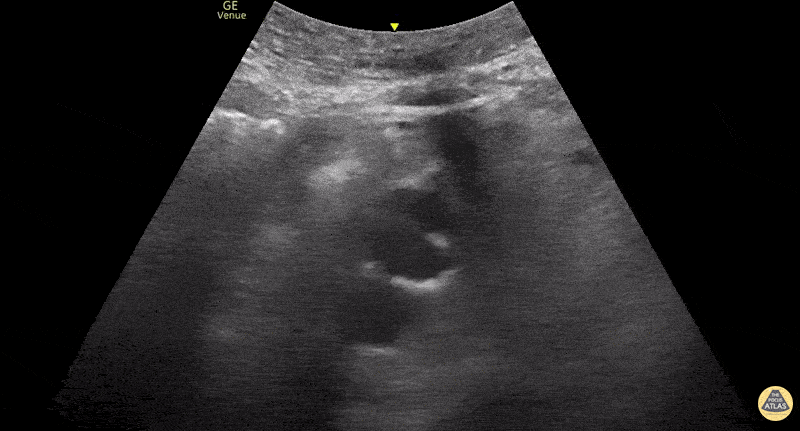

Aorta - Aortic Dissection Flap in Desceding Aorta

Flap seen in the descending aorta consistent with aortic dissection Contributed by: Dimitri Livshits DO, Ultrasound Fellow; Jane Belyavskaya MD, Ultrasound Fellow; Chris Hanuscin MD, Ultrasound Division Director (Kings County/SUNY Downstate)